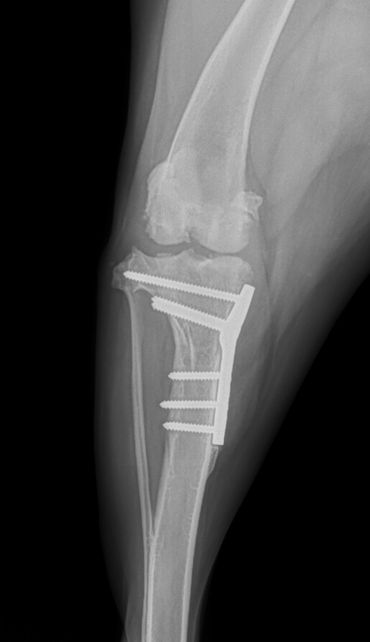

If your pet has a torn CCL they will usually be uncomfortable and manifest this as limping. They often prefer to limit their own activity level due to the pain and may be more sedentary. When a CCL tear is diagnosed, usually the best option is to stabilize the stifle surgically for the best outcome. One technique commonly performed for decades has been the Tibial Plateau Leveling Osteotomy (TPLO). The TPLO was designed to eliminate the tibial thrust motion that occurs with a CCL tear and thus return stability to the stifle for return to function. The TPLO procedure is very technical and thus is best performed by experienced surgeons. Initially the TPLO was only taught by the original designer of the procedure, Slocum Enterprises, and luckily Dr. House managed to complete this training program before it ended. To perform a TPLO procedure a bone cut (osteotomy) is made in the shin bone (tibia) near the knee. This cut is curved and allows a change in the angle within the stifle to alter the forces as mentioned above. Once the cut is made and the bone is rotated, a metal plate and screws are placed to hold the bone in its new position while it heals. These implants are usually left in place for life and are only removed if a reaction or infection should develop, which is generally uncommon. Since a cut is made in the bone for this procedure, patients must go through a rest period while the bone heals adequately for normal activity again. It is critical that patients rest to avoid breaking their bone or the implants. The post-operative instructions typically followed are below. If your pet has been diagnosed with a CCL tear, a TPLO may be recommended. This procedure is usually best performed in pets weighing 50 pounds and above. It can be performed in animals under 50 pounds, however, and this can be determined at a surgical consultation. Dr. House performs the TPLO procedure almost daily and would be happy to meet with you and your pet to discuss and perform the procedure accordingly at your local veterinary clinic.

At 8 weeks following surgery, your pet should return to their vet for x-rays. The x-rays are done to assess the bone healing process and to ensure the implants placed have remained unchanged. Your pet's ambulation will also be assessed to ensure healing is occurring as expected. Once this visit is completed, and your pet is doing well, you may then start increasing your leash walks duration and frequency for 4 additional weeks. By the 12 week timepoint after surgery, your pet's bone should be adequately healed to run and play like they used to! Remember that following the recovery process strictly is critical to healing well and that each patient may heal differently. If you ever have concerns about the recovery of your pet, please don't hesitate to ask. We all want your pet to heal well from their surgery and be happy and healthy again!